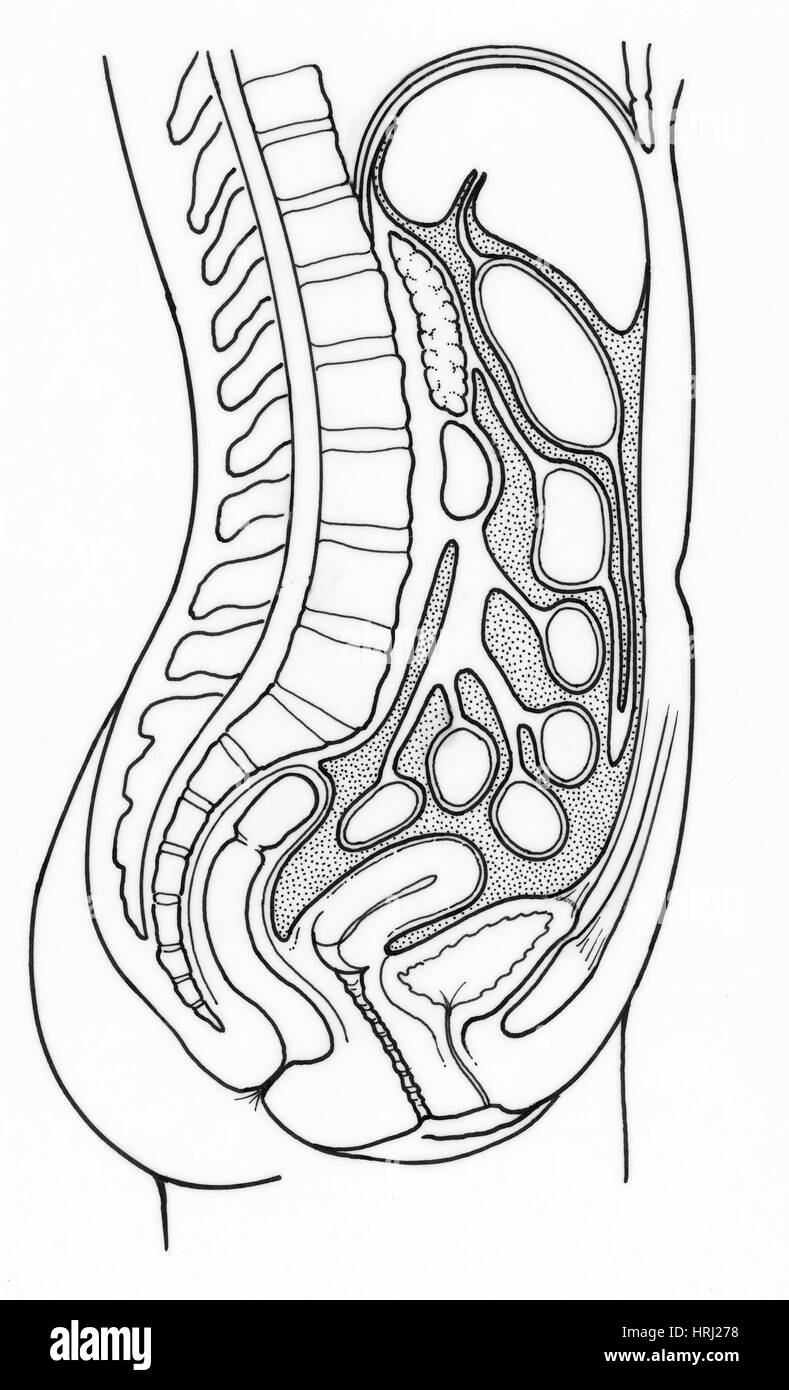

Illustration of Female Internal Organs Stock Photohttps://www.alamy.com/image-license-details/?v=1https://www.alamy.com/stock-photo-illustration-of-female-internal-organs-135006572.html

Illustration of Female Internal Organs Stock Photohttps://www.alamy.com/image-license-details/?v=1https://www.alamy.com/stock-photo-illustration-of-female-internal-organs-135006572.htmlRMHRJ278–Illustration of Female Internal Organs

Illustration of Female Internal Organs Stock Photohttps://www.alamy.com/image-license-details/?v=1https://www.alamy.com/stock-photo-illustration-of-female-internal-organs-135006887.html

Illustration of Female Internal Organs Stock Photohttps://www.alamy.com/image-license-details/?v=1https://www.alamy.com/stock-photo-illustration-of-female-internal-organs-135006887.htmlRMHRJ2JF–Illustration of Female Internal Organs